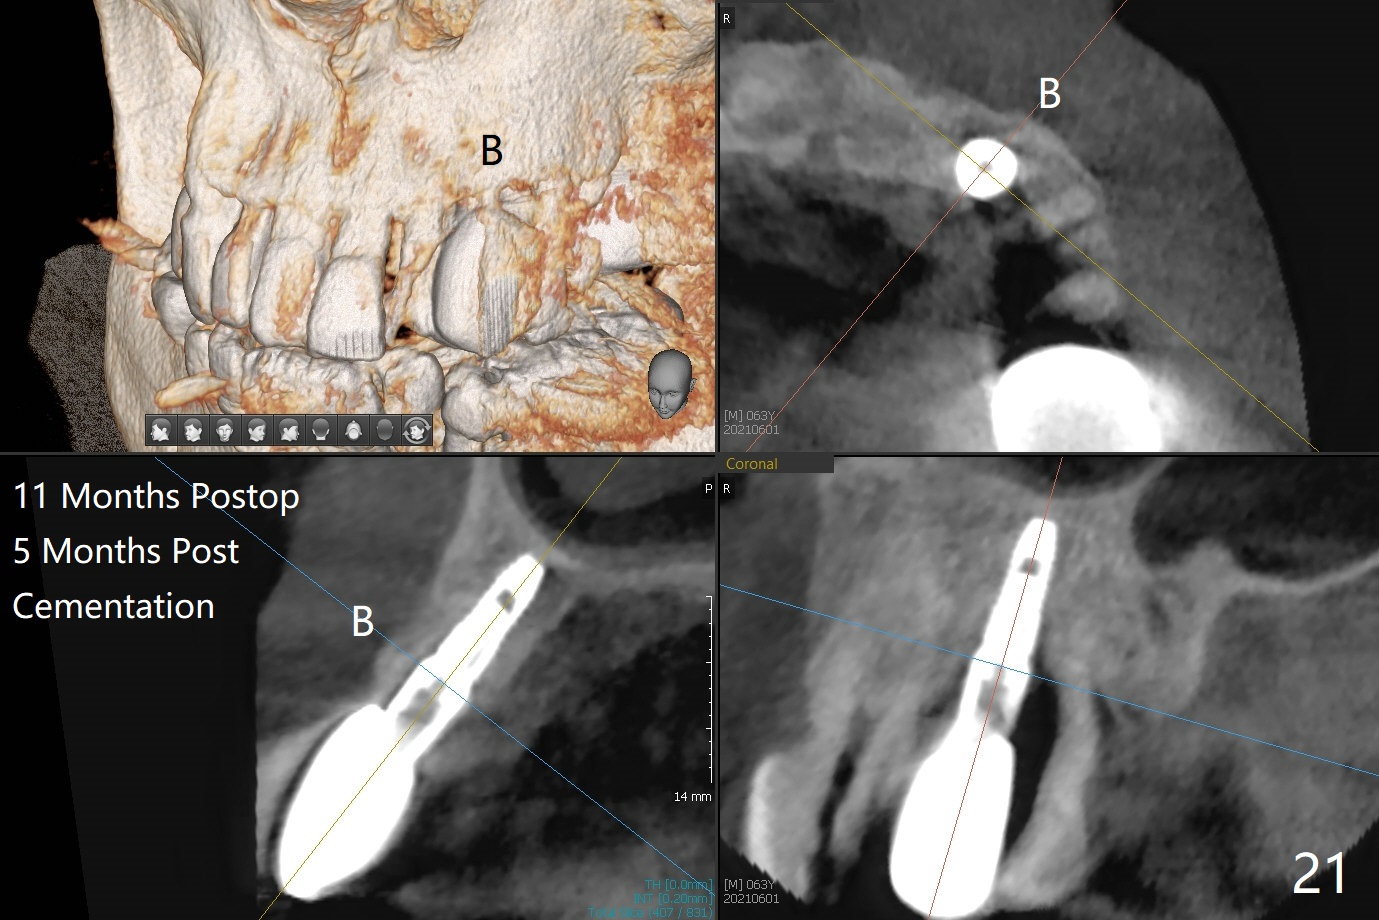

A 62-year-old man with generalized chronic periodontitis returns with chief complaint of loose tooth at #11 (Fig.1). Although a buccal fistula (Fig.1 <) is closer to #12 than to #11, percussion is more severe at #11 than 12. The buccal plate of #11 is missing, but it is possible to place a narrow immediate implant because of the wide alveolus (Fig.2). Since the gingiva is ~ 10 mm long, a mill abutment is to be used (Fig.3,5). In fact the fistula communicates with #11 extraction socket. After debridement, osteotomy is initiated (Fig.4) for a 3.8x10 mm implant ~ 35 Ncm, followed by seating a 4.5x2 mm mill abutment (Fig.5). Abundant sticky bone is placed in the remaining socket (for buccal plate reconstruction) and against the root surface of the neighboring teeth (Fig. 6 * (#10,12)). Finally 2 pieces of PRF membranes are utilized to facilitate repair of the buccal soft tissue defect (Fig.7 *). The root prominence of the canine seems to be maintained by the bone graft (Fig.8 C). Acrylic dressing holding the PRF membranes in place remains in situ with the healthy gingiva buccal (Fig.9) and palatal (Fig.10) 11 days postop. Note the acrylic locking into the undercuts of the neighboring teeth (*). 经过一段摸索发现离心每分钟1500转5分钟后,抽取上清液,接着再离心10分钟剩余上清液就形成血小板块,压制后便是血小板膜,后者似乎有助于软组织愈合,而上清液用来制备骨块,帮助硬组织生长。利用这个原则讨论以下病例治疗。The gingival margin gains ~ 5 mm 6 weeks postop when the acrylic dressing is removed (Fig.11,12 (<: previous one), as compared to Fig.7,8). 治疗结束时尖牙牙龈缘高于第一双尖牙(图七,八),六个星期后,尖牙牙龈缘却低于双尖牙(图十一,十二(箭头:原始牙龈缘))。术后2.5,4.5月基台周围牙龈似乎能与钛合金附着,防止细菌进入深部植体(图十三,十四)。临时牙冠脱落多次,可能与mill abutment太光滑有关,所以颊侧,舌侧磨成平面(图十四)。取模时好像不必取出基台清洗(仿佛没有炎症),原位用树脂延长基台。术后5个月CT显示颊侧骨板再生(图十六-十八)。取模时并没有用树脂加长基台;粘固时,牙冠颜色理想,但是照片中并不是如此(图十九,二十),颊侧骨板没有塌陷。术后11个月基台颊侧骨板没有萎缩(图二十一:B);3d图像:骨壁完全形成(图十六对比:部分形成)。密度也增高(图二十二:B),与术后五个月比较(图十七)。术后十一个月,粘固后五个月角化龈存在(图二十三),牙冠颈部有金属颜色透出,是因为二段式基台太粗了(最细4.5毫米),可以请实验室在牙冠内部涂opaque material而减轻。